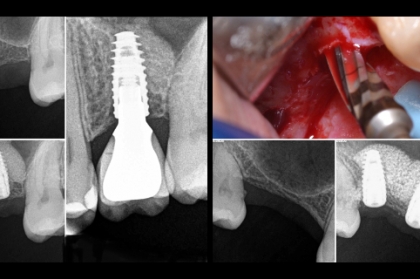

Elevação de seio maxilar por abordagem crestal com osseodensificação 21 de setembro de 2020, 21:00h Faro

Implantes em setores posteriores - possibilidades de reabilitação (streaming) 18 de maio de 2020, 21:00h